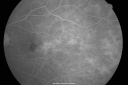

FLUORESCEIN ANGIOGRAPHY: Fluorescein angiography shows enlargement of the foveal avascular zone in each eye and also a temporal capillary drop in each eye.